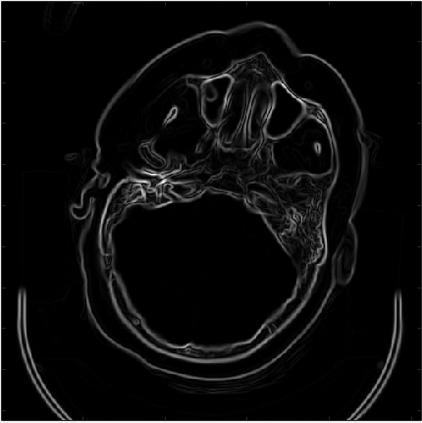

In this work, we present Eformer - Edge enhancement based transformer, a novel architecture that builds an encoder-decoder network using transformer blocks for medical image denoising. Non-overlapping window-based self-attention is used in the transformer block that reduces computational requirements. This work further incorporates learnable Sobel-Feldman operators to enhance edges in the image and propose an effective way to concatenate them in the intermediate layers of our architecture. The experimental analysis is conducted by comparing deterministic learning and residual learning for the task of medical image denoising. To defend the effectiveness of our approach, our model is evaluated on the AAPM-Mayo Clinic Low-Dose CT Grand Challenge Dataset and achieves state-of-the-art performance, $i.e.$, 43.487 PSNR, 0.0067 RMSE, and 0.9861 SSIM. We believe that our work will encourage more research in transformer-based architectures for medical image denoising using residual learning.